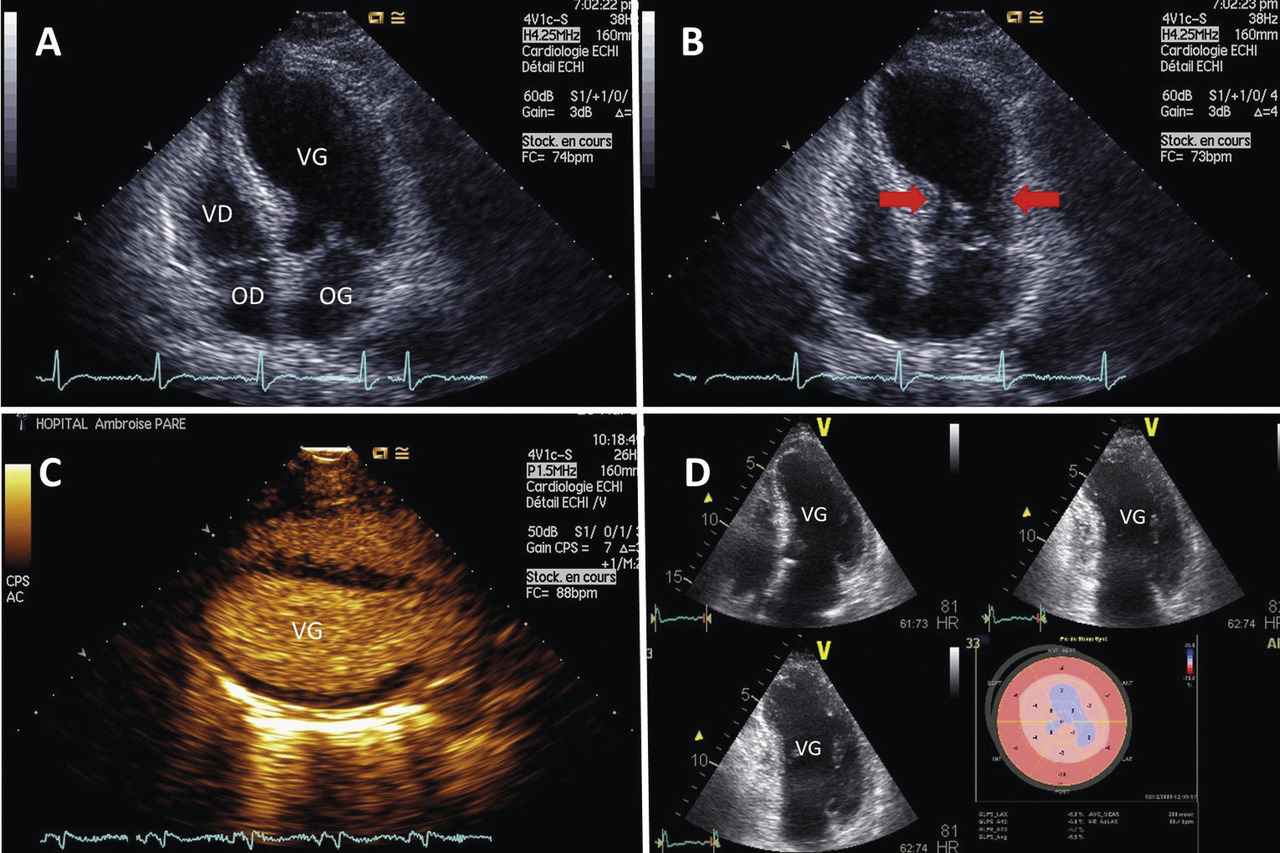

La coronarographie éventuellement couplée à une ventriculographie permet d’éliminer le SCA et d’affirmer le Takotsubo sur l’aspect pathognomonique de dysfonction VG (fig. 3 ).

La coronarographie éventuellement couplée à une ventriculographie permet d’éliminer le SCA et d’affirmer le Takotsubo sur l’aspect pathognomonique de dysfonction VG (

Forme typique : akinésie des portions apicales et moyennes du VG, seule la collerette basale est contractile (70 à 80 % des cas ;fig. 3 ).5

Forme typique : akinésie des portions apicales et moyennes du VG, seule la collerette basale est contractile (70 à 80 % des cas ;

Forme typique : akinésie des portions apicales et moyennes du VG, seule la collerette basale est contractile (70 à 80 % des cas ; fig. 3).5

Forme médiane (20 à 30 %) : seules les portions moyennes sont akinétiques.

Forme inversée (1 %) : akinésie des portions basales.

La forme focale, récemment décrite, est exceptionnelle.